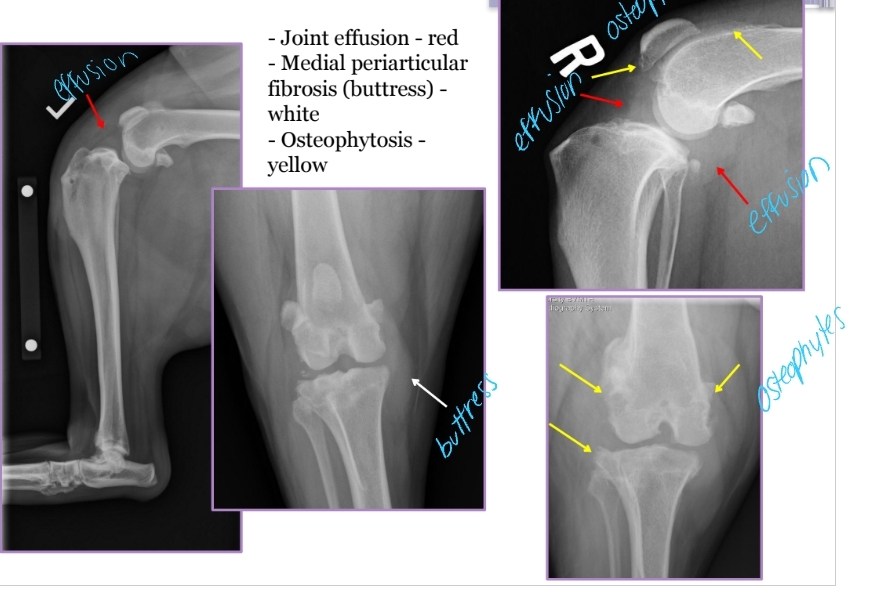

Cranial Cruciate Ligament Disease Diagnosis

PE: Crouched hindlimbs, external rotation of affected limb, Failed “sit test”

Acute clinical presentation

Meniscal Click: Torn meniscus pops due to shear with range of motion

Radiographs: Joint effusion, Medial periarticular fibrosis(medial buttress), Osteophytosis, Cranial drawer placement, OA